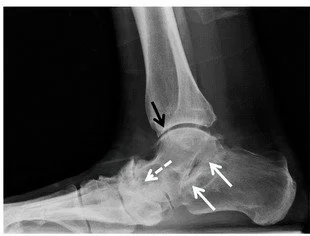

Weight-bearing X-rays are typically used to confirm the diagnosis and may demonstrate joint space narrowing, bone spurs, deformity, or post-traumatic changes. In more complex cases, CT scans may be obtained to better evaluate joint surfaces and assist with surgical planning.